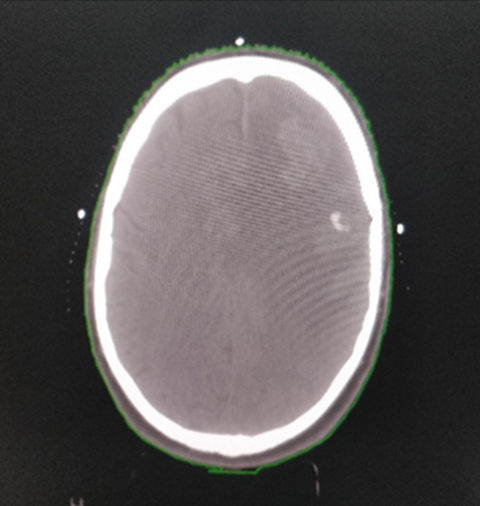

A 73-year-old male, diagnosed with ca rectum in 2018 presented with complaint of persistent worsening headaches, nausea, vomiting and weakness right upper limb. On neurological examination, power right upper limb was 3/5. Rest of physical and systemic examination was normal. CECT head showed heterogeneously enhancing lobulated mass lesion in left frontal cortex measuring 3.2x2.7x3.0 cm in maximum dimension (Figure 1).

Figure 1: CECT head showing a heterogeneously enhancing lobulated mass lesion in the left frontal cortex

Figure 2: CECT Image of the Head Demonstrating a Heterogeneously Enhancing Lobulated Mass Lesion in The Left Frontal Cortex